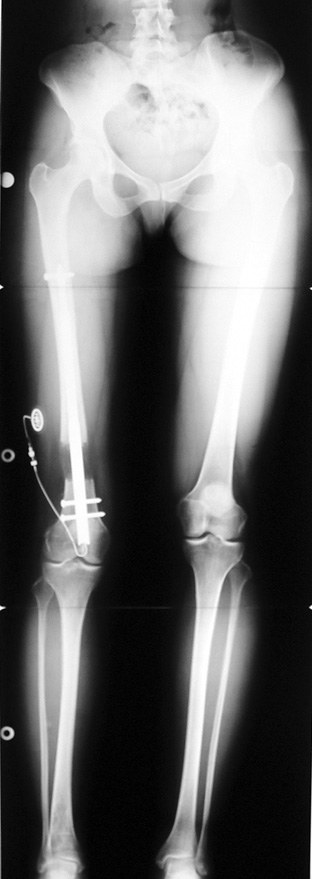

Case 2